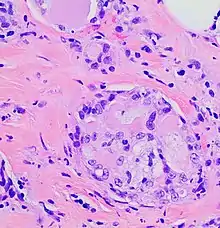

Histopathology of secretory carcinoma, high magnification. H&E stain. It characteristically shows nests of tumor surrounded by stroma, where the nests have microcystic and adenoid structures with eosinophilic secretions.